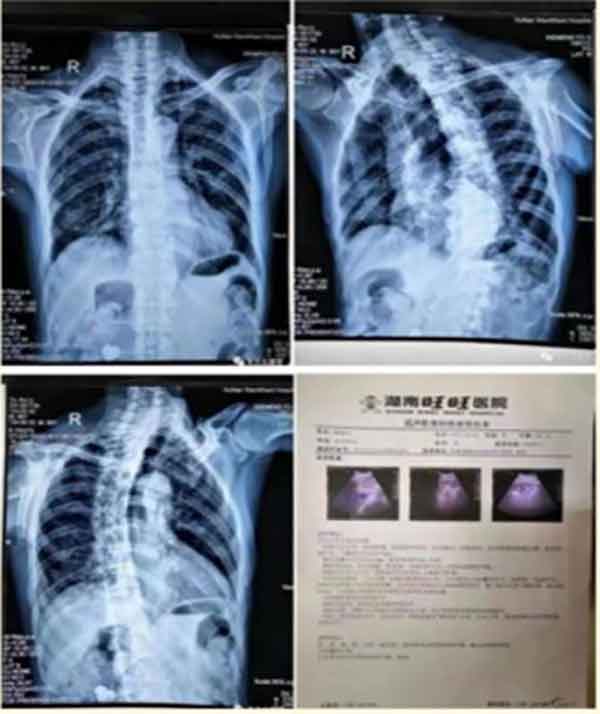

患者:喻修立,右侧8-12肋的肋骨骨折,右侧的腕关节半脱位,右侧肩关节关节挫伤

喻修立,86岁,2018.12.18日他儿子把他送来我们店康复,他是当天摔了一跤外伤引起的右侧8-12肋的肋骨骨折,右侧的腕关节半脱位,右侧肩关节关节挫伤。当时来我们这里他的右手腕关节是不能活动的,稍微大一点范围的活动就会疼痛剧烈,右肩部不能上抬,不能平举。右肋部疼痛剧烈,呼吸的时候稍微深一点的呼吸,胸部就会有牵拉痛和刺痛感,走路的时候腰不能伸直,两个人扶着他弓着腰进来的。我首先帮他把手腕关节半脱位的地方做了复位,肩部做了疏理,肋骨骨折处做了整复,用的朱龙筋骨冷敷凝胶,外敷秘方膏贴。做完一次康复之后,当时背部基本可以伸直了,手腕也可以活动了,呼吸没有刺痛感了。之后每隔三天做一次康复,外涂朱龙筋骨冷敷凝胶,外敷秘方膏贴。2019年1月21日,经过34天的康复,患者自己说已经痊愈了,手和背部、肋骨处没有疼痛感了,可以正常活动了。在患者的要求下,我们结束了康复疗程。

2019年1月21日,喻修立爷爷自己感觉已经痊愈了,没有疼痛感了。腰可以正常伸直,手臂可以正常抬举。